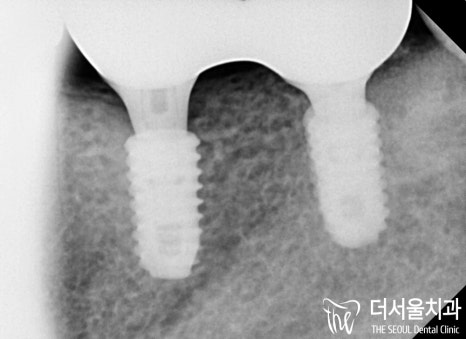

다행히 골 유착도 잘 되어 있고

크라운도 예쁘게 잘 만들어졌네요.